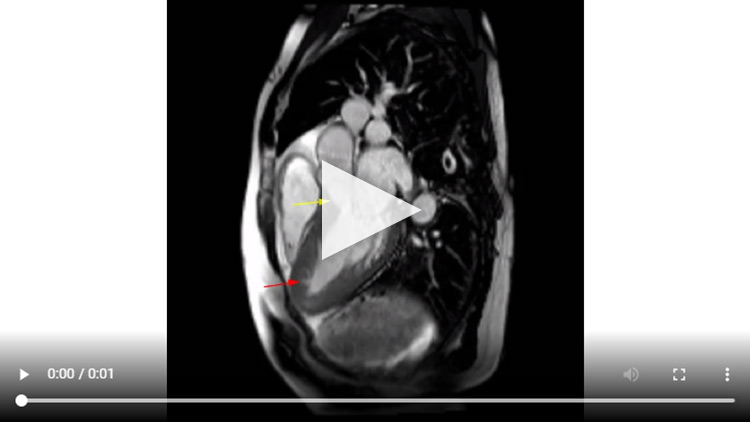

Vidéo 1 : Séquence Ciné-IRM coupe 2 cavités

Vidéo 2 : Séquence Ciné-IRM coupe 3 cavités

Vidéo 3 : Séquence Ciné-IRM coupe 3 cavités

Vidéo 4 : Séquence Ciné-IRM coupe petit-axes

Figure 5 : Séquence Ciné-IRM réalisée après injection de Gadolinium

Vidéo 5 : Ciné 3 Cavités